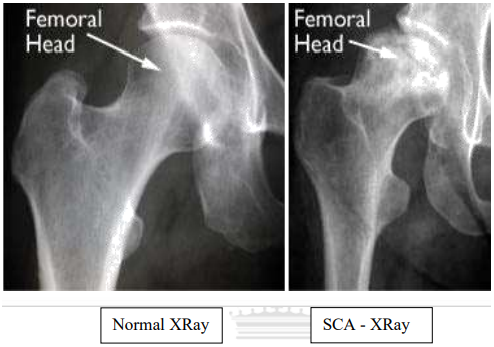

Некроз тазобедренного сустава: Фотографии и особенности лечения